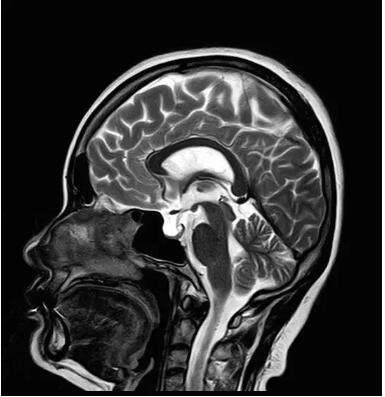

圖:搭載Pure射頻鏈全新一代1.5T磁共振

佳能磁共振推出了全新一代Vantage Elan1.5T磁共振,這款日本原裝進(jìn)口的 1.5T磁共振,集當(dāng)今磁共振創(chuàng)新科技成果于一身: